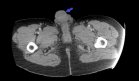

Estudios adicionales, como la detección de anticuerpos contra la 21-hidroxilasa y una tomografía computarizada de glándulas suprarrenales, pueden realizarse para confirmar la causa subyacente, aunque en este caso la presentación clínica y los hallazgos de laboratorio fueron suficientes para establecer el diagnóstico.